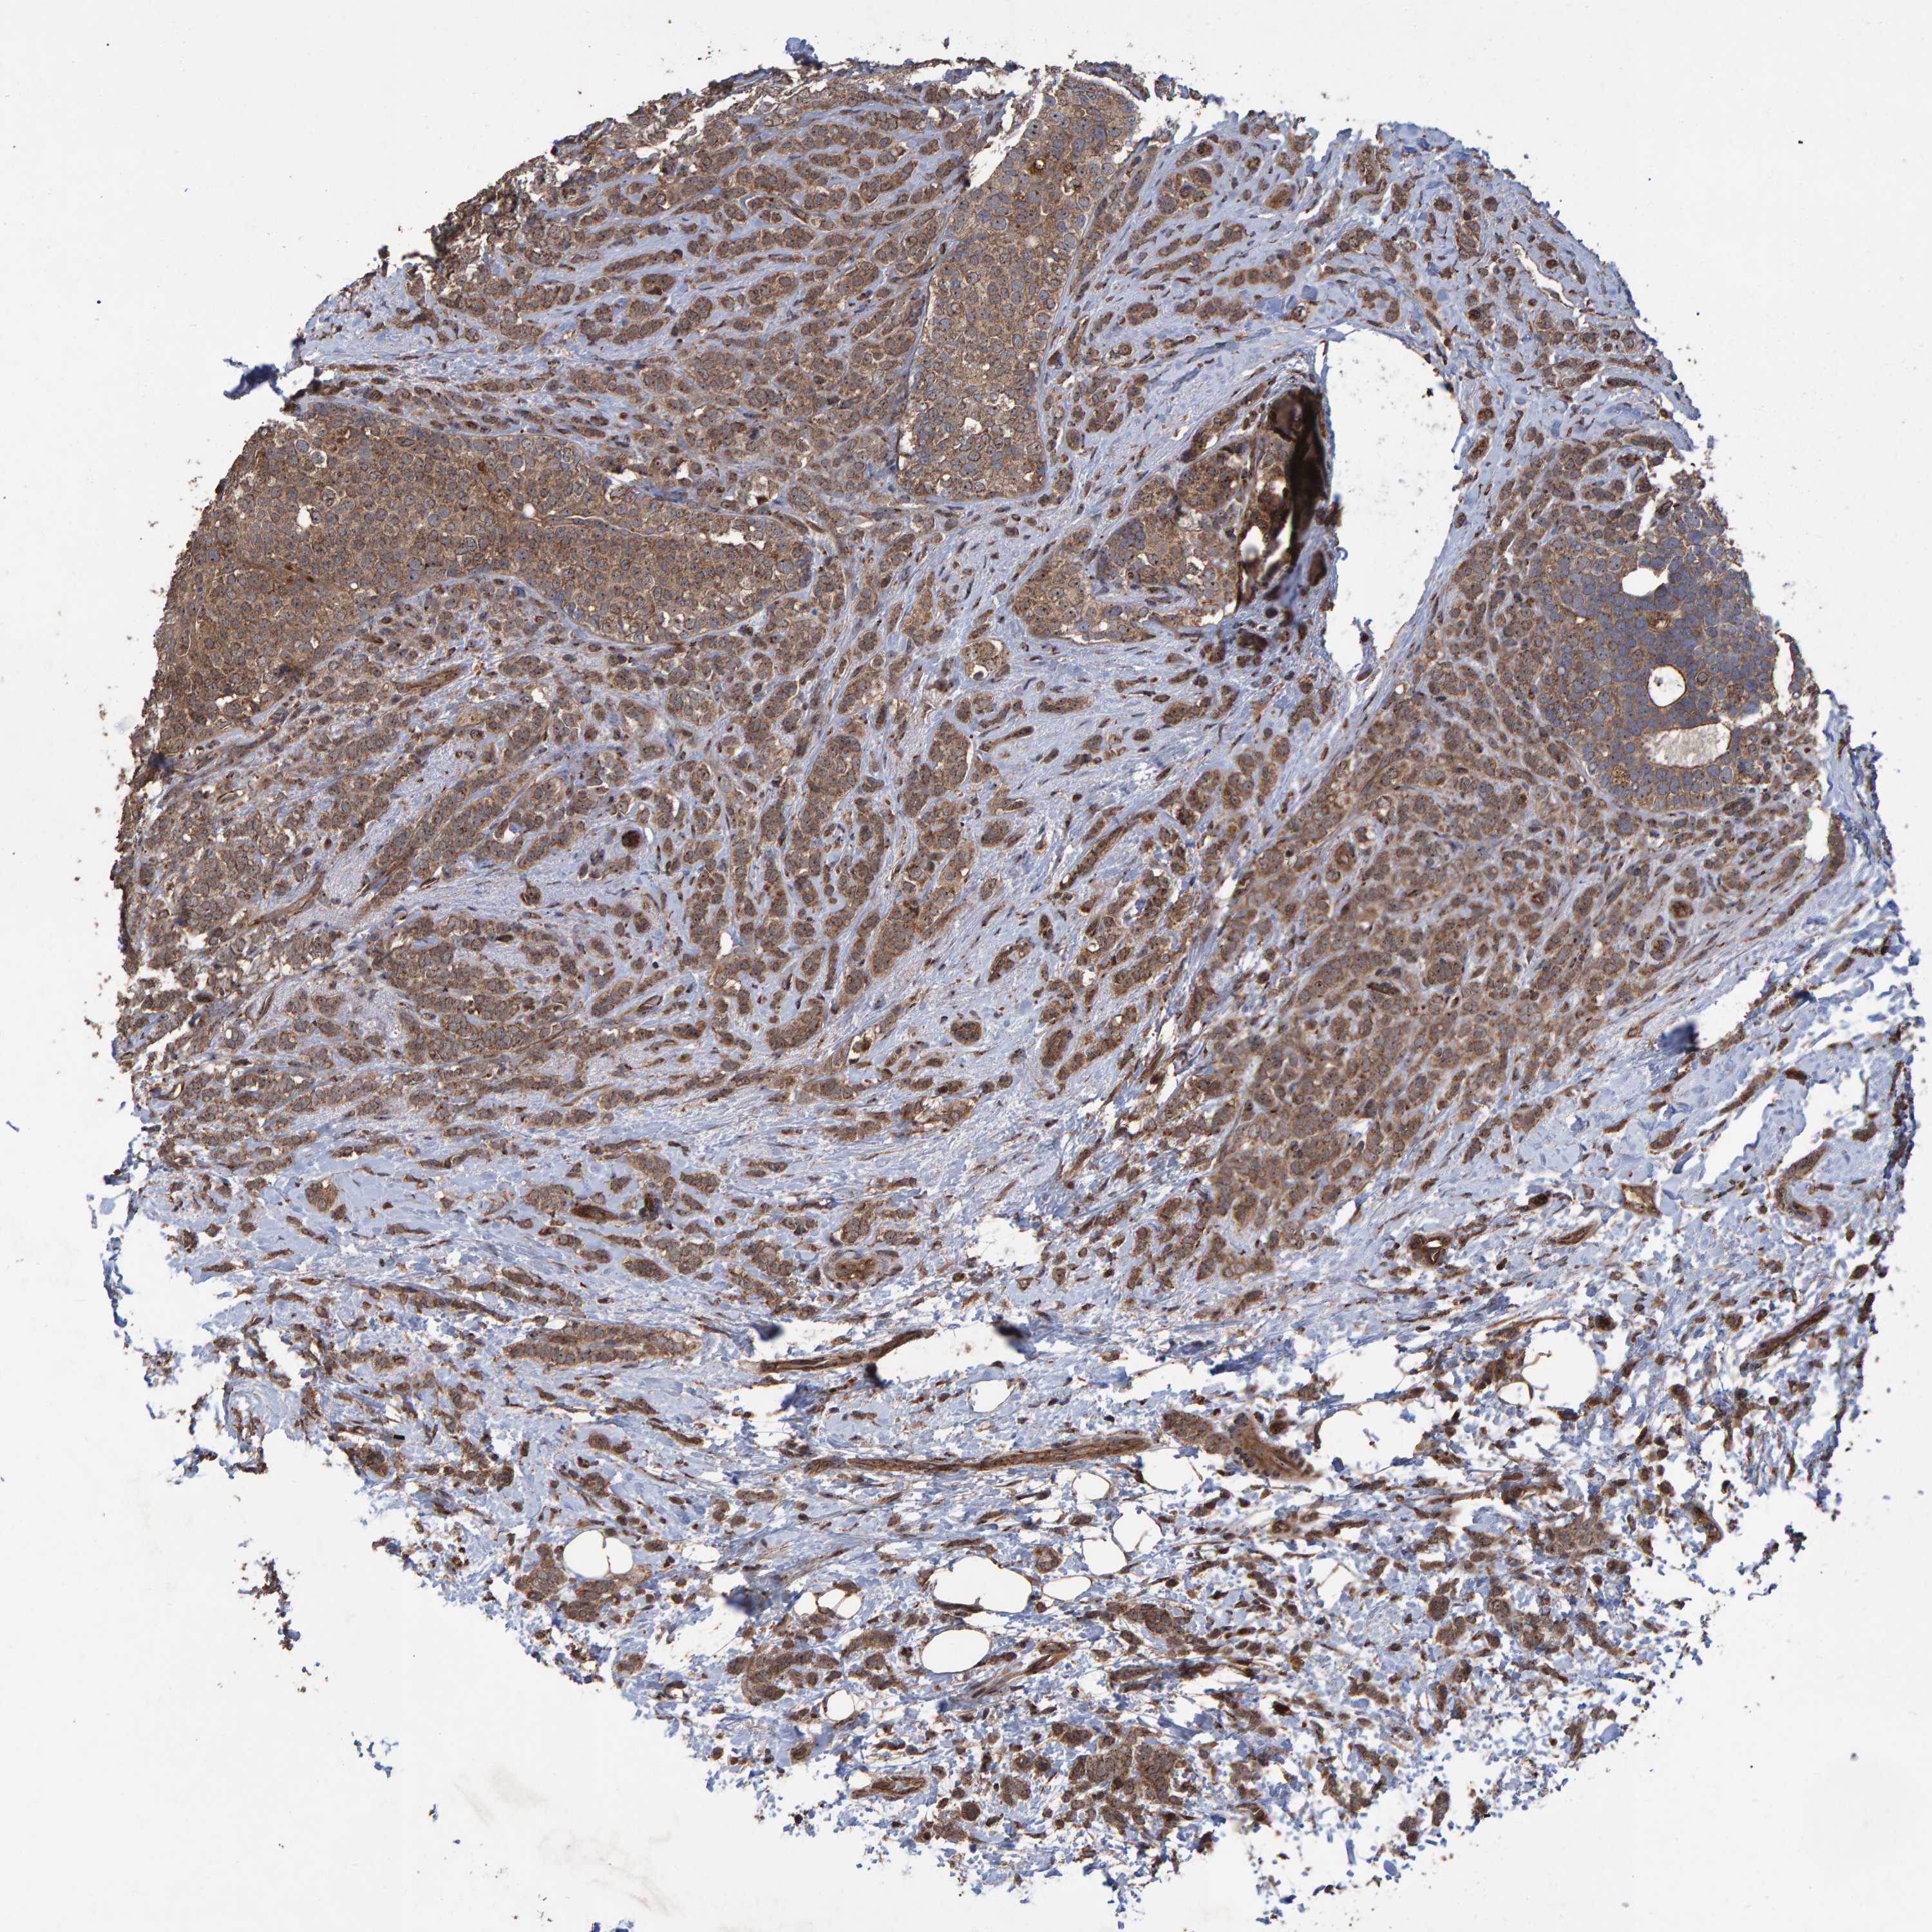

CANCER BREAST CANCER Show tissue menu

BRCA TCGA BRCA VALIDATION PROTEIN EXPRESSION